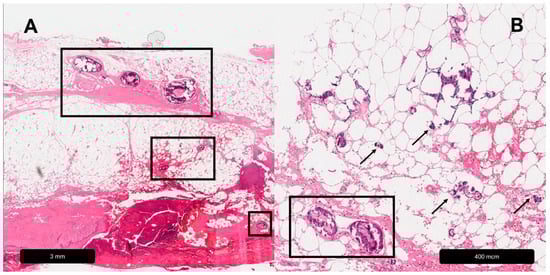

Figure 3.

Arteriolosclerotic ulcer of Martorell. (A) Black rectangles = calcification. (B) Black rectangle = subintimal hyalinization.